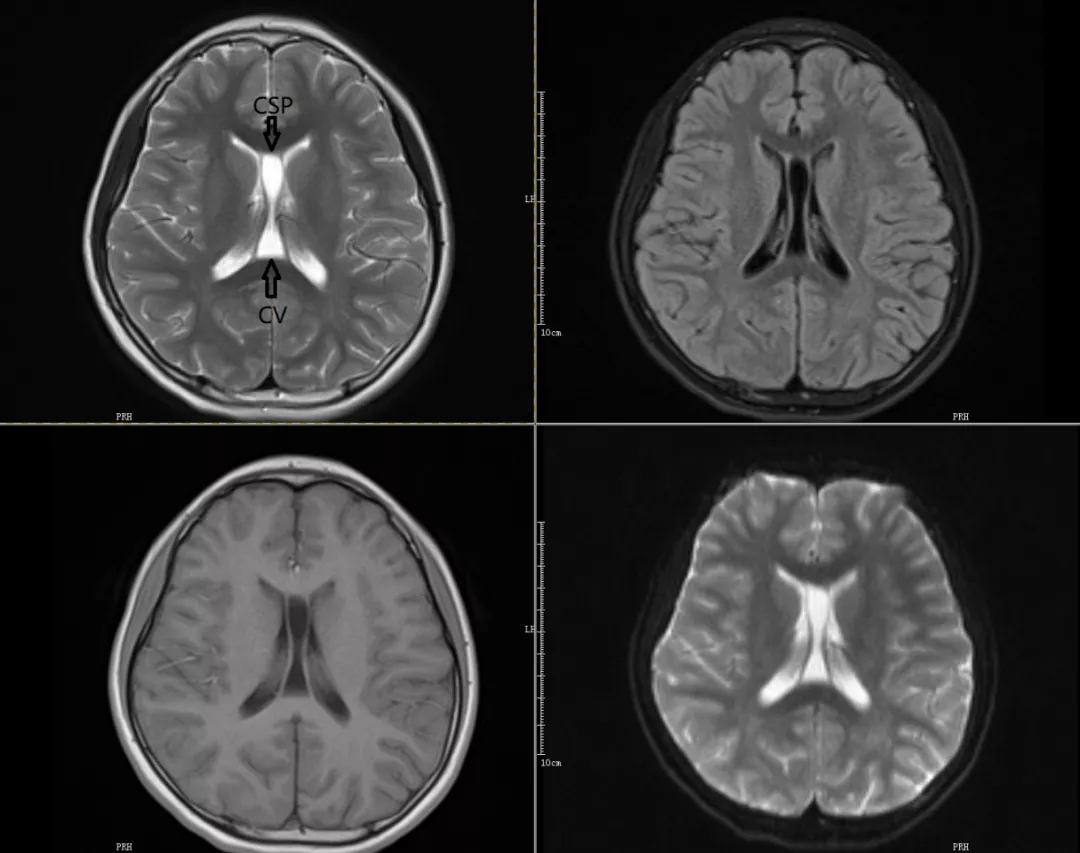

CASE1

透明隔间腔及Vergae腔同时存在

MRI表现:轴位上,透明隔间腔位于两侧侧脑室额角之间,其内为脑脊液信号,可呈条带状、三角形或类似梯形,边缘清楚,两侧壁多平行,两侧壁之间的宽度约1~10mm。若透明隔侧壁向两侧弯曲甚至膨隆,失去正常的平行状态,且侧壁间的距离10mm,则称其为透明隔囊肿。Vergae腔位于透明隔间腔之后,双侧侧脑室体部之间,表现为前窄后宽的纵形腔隙结构,其内为脑脊液信号。两者一般同时存在,呈条带状,双侧的腔壁大致平行。

透明隔间腔(CSP)又称第五脑室,Vergae腔(CV)又称穹窿腔或第六脑室。儿童多见,随年龄增长这些腔隙多数将逐渐闭合,仅少数永存于成年人。两者均无室管膜及脉络丛组织,所以均不属于真正的脑室系统。实际中一般将两者视为同一结构的前、后腔。两者属于正常解剖变异,通常无临床意义。